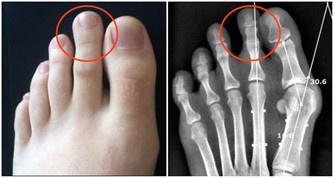

有人換個燈泡接觸了上面的灰塵會得紫癜……

過敏表現常在接觸過敏原半小時至數小時後出現。一般表現如下:煩躁、心慌、胸悶、咽部不適、視物模糊、疲勞、易激惹、緊張、自控力下降、忍耐力下降、情緒失控、皮膚潮紅、紫癜、皮疹、耳道濕潤、鼻塞、鼻涕、鼻塞、噴嚏、眼瞼浮腫、腹痛、腹瀉、多汗、咳嗽,哮喘,呼吸淺快、血壓降低、關節冷痛等等。可見於多種過敏性疾病(如過敏性哮喘、咳嗽、紫癜、皮炎、鼻炎)、一些易激綜合徵(比如腸易激,還有情緒易激等等)、濕疹、痛經、咽炎等等。